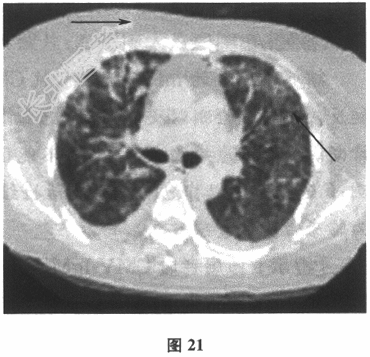

- [材料题] 患者男性,58岁。肾衰竭5年,肾移植术后2个月。因"发热、呼吸困难5天"入院。患者5天前无明显诱因出现发热,体温最高可达39℃,伴喘憋和畏寒,无明显寒战,偶有咳嗽,但无明显咳痰,有发热且感轻度头痛,无意识障碍,无胸痛,无咯血,未正规诊治,自服"退热药",仍反复发热。查体:体温38.8℃,脉搏110次/分,呼吸频率30次/分,血压130/90mmHg(1mmHg=0.133kPa),两肺呼吸音清晰,未闻及干湿啰音。血常规检查:白细胞计数5.8×109/L,中性粒细胞0.888,血红蛋白122g/L。未吸氧状态下动脉血氧分压50mmHg。胸部X线片:双肺见斑片状高密度影,右侧肋膈角模糊。

胸部CT:示双肺多发斑片、磨玻璃影,伴小叶间隔增厚和双侧少量胸腔积液(图20,图21)。